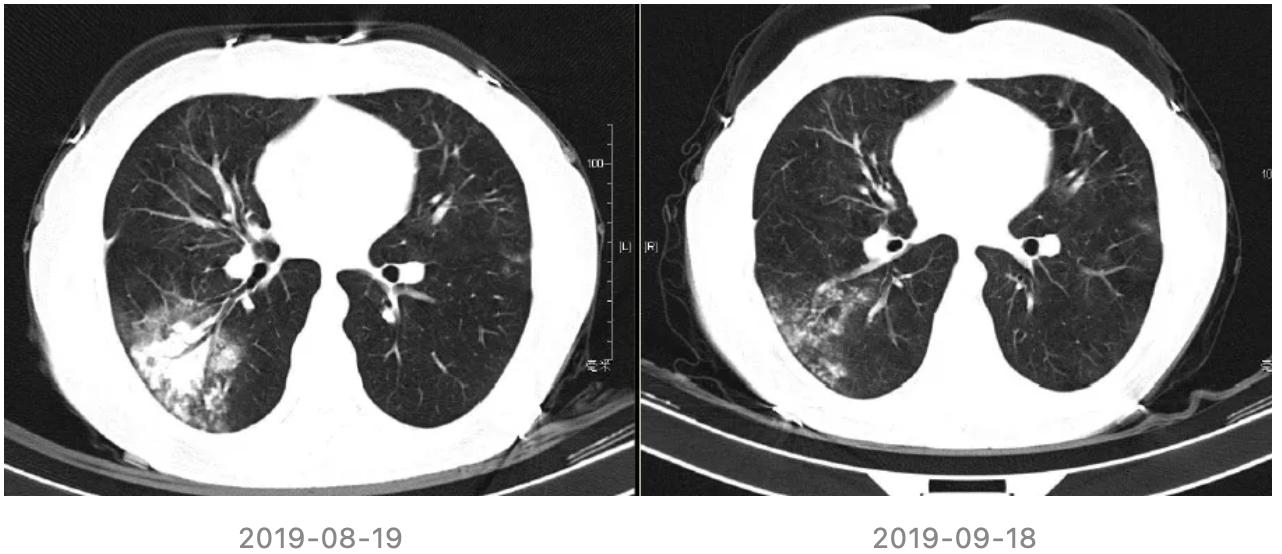

继续用药随访情况:

患者2019年6月和7月随访胸部CT,较前2019-05-13片相仿。

2019-08-19来院复诊,无咳嗽,无发热,无气喘。入院后查血常规、肝肾功能、电解质、心肌标志物、免疫球蛋白、细胞免疫、肿瘤标志物均正常,CRP:7.4mg/l,ESR 18mm/H。

胸部CT(2019-08-19):右下肺新发炎症病变;余两肺炎性病变,较前相仿。

再次调整治疗方案

开始予四联抗结核:异烟肼0.3g qd po,利福平0.45g qd po,乙胺丁醇0.75g qd po,吡嗪酰胺0.5g tid po

停用硫唑嘌呤;糖皮质激素逐步减量至停用。

转归:

(1)抗结核治疗1月后随访胸部CT:

(2)抗结核治疗1年随访胸部CT: